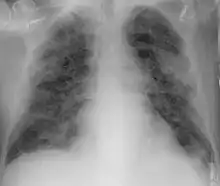

Imaging

Chest CT scans may be helpful to diagnose COVID‑19 in individuals with a high clinical suspicion of infection but are not recommended for routine screening.[160][172] Bilateral multilobar ground-glass opacities with a peripheral, asymmetric, and posterior distribution are common in early infection.[160][173] Subpleural dominance, crazy paving (lobular septal thickening with variable alveolar filling), and consolidation may appear as the disease progresses.[160][174] Characteristic imaging features on chest radiographs and computed tomography (CT) of people who are symptomatic include asymmetric peripheral ground-glass opacities without pleural effusions.[175]

Many groups have created COVID‑19 datasets that include imagery such as the Italian Radiological Society which has compiled an international online database of imaging findings for confirmed cases.[176] Due to overlap with other infections such as adenovirus, imaging without confirmation by rRT-PCR is of limited specificity in identifying COVID‑19.[175] A large study in China compared chest CT results to PCR and demonstrated that though imaging is less specific for the infection, it is faster and more sensitive.[159]